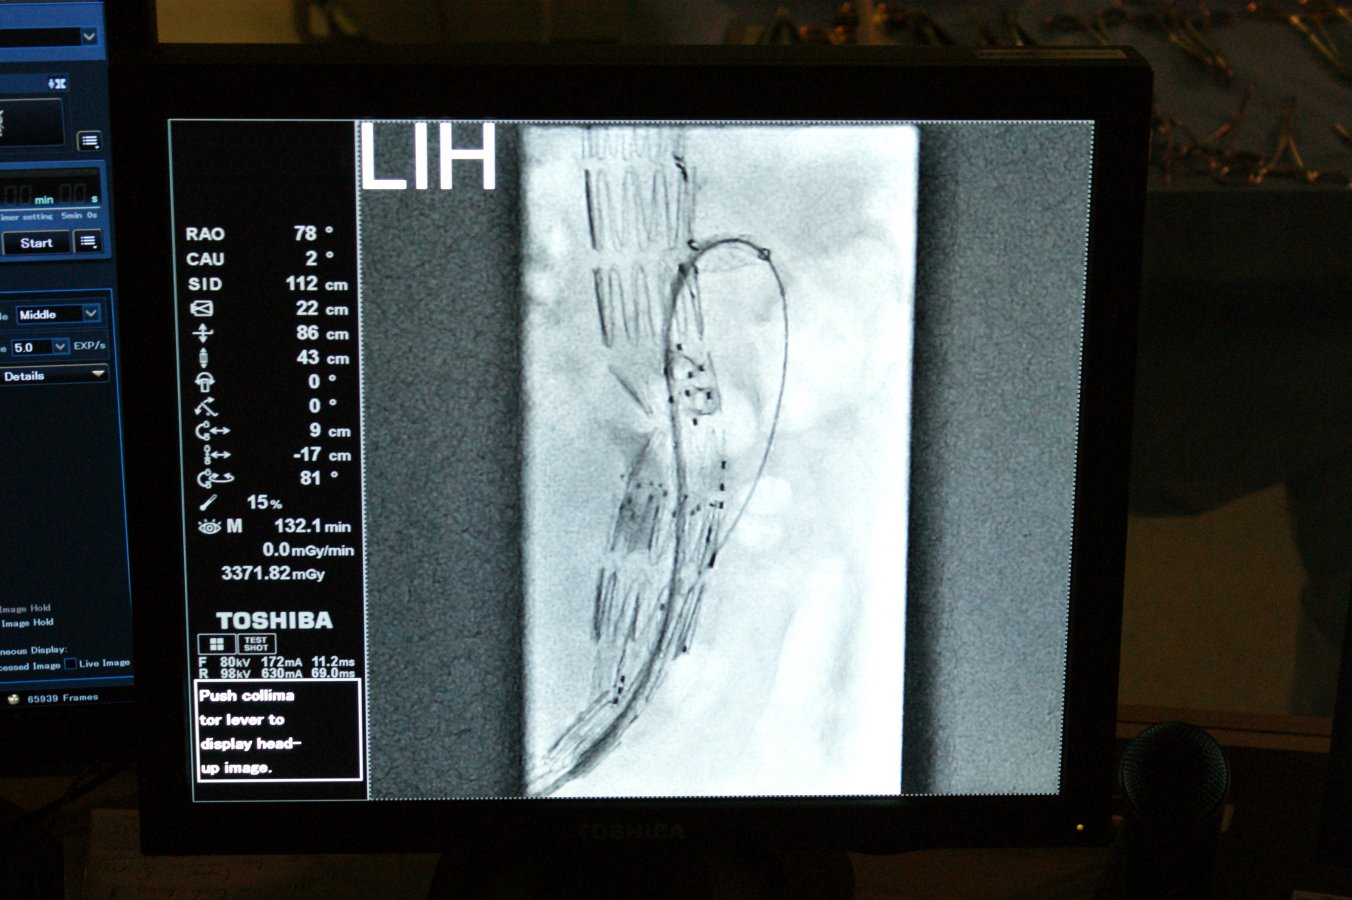

Teraz białostoccy lekarze rozpoczęli operowanie przez „dziurkę od klucza” - do aorty dostają się przez pięciocentymetrowe nacięcia w pachwinach. Wcześniej jednak do takiego zabiegu muszą się odpowiednio przygotować.

- Po zdiagnozowaniu tętniaka kierujemy pacjenta na angiografię CT, czyli tomografię komputerową naczyń krwionośnych - tłumaczy dr hab. Jerzy Głowiński, p.o. kierownika Kliniki Chirurgii Naczyń i Transplantacji w USK. - Wynik przesyłamy do firmy, która wytwarza indywidualnie dopasowane do każdego pacjenta stentgrafty, czyli protezy wewnątrznaczyniowe. Ten wynik jest obrabiany komputerowo, a następnie stentgraft jest szyty na miarę w Nowej Zelandii. Po sześciu tygodniach dostajemy gotowy, dopasowany anatomicznie dla danego pacjenta stentgraft fenestrowany, czyli taki, który ma specjalnie przygotowane otwory na odchodzące od aorty naczynia.

Jak mówi dr hab. Jerzy Głowiński ta precyzja jest bardzo ważna: każdy człowiek ma w innym miejscu odejścia tętnic nerkowych czy krezkowych i nawet jeden milimetr ma tu znaczenie.

Nowej metody operowania białostoccy lekarze uczą się od prof. Piotra Kasprzaka z Kliniki Chirurgii Naczyń Szpitala Uniwersyteckiego w Regensburgu. Prof. Kasprzak ma największe w Europie doświadczenie w tego typu operacjach: do tej pory przeprowadził i nadzorował ponad tysiąc takich operacji. Wspólnie wykonali już dwa zabiegi i dziś (11 października) planują wykonać kolejny trzeci. Kolejnych dwóch pacjentów białostoccy chirurdzy naczyniowi, dr hab. Jerzy Głowiński i dr Adam Płoński, planują samodzielnie zoperować do końca tego roku. Mają nadzieję, że tego typu zabiegi będą stale wykonywane w Białymstoku. Problemem jest bowiem cena stentgraftów. Do takiej operacji potrzebne są dwa stentgrafty „szyte na miarę” oraz 3-4 standardowe stentgrafty do naczyń trzewnych. Wszystko to kosztuje około 200 tys. zł.